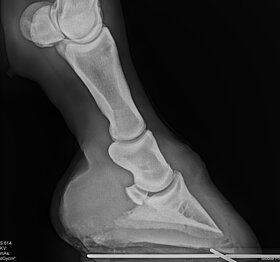

Mit akkubetriebenen Röntgengeräten können wir bei orthopädischen Untersuchungen oder Verletzungen (auch auf der Koppel oder an einem Offenstall) ohne Strom direkt vor Ort röntgen und die Bilder gleich auswerten.